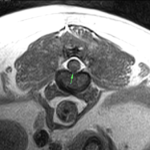

コーギー犬には椎間板ヘルニアや変性性脊髄症が起こりやすいことはよく知られています。コーギーさんが日常生活には支障はないが、ごく軽度のふらつきがあるので主治医からMRI検査を勧められ来院しました。MRIでは軽度の椎間板ヘルニアが確認されました。この程度であれば外科的手術は適応ではありません。しかし、3箇所にヘルニアがあることから同時に3箇所に処置を行うことになりました。正確に行うために外科用イメージを使いながら3部位の病変部位に経皮的に椎間板を狙ってレーザーファイバーを刺入します。このPLDDは低侵襲ではありますが、全身麻酔下で処置を行いますので、通常は翌日の退院となります。しかし、特に運動制限などは必要としていません。